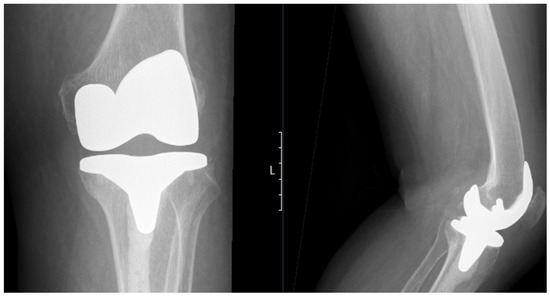

Figure 3.

Postoperative standing anteroposterior (left) and lateral (right) X-rays of the left knee showing the total knee prosthesis in situ. Notably, there is extensive cement penetration into the tibial canal, reflecting underlying bone brittleness associated with ochronotic arthropathy. No signs of aseptic loosening or periprosthetic fractures.